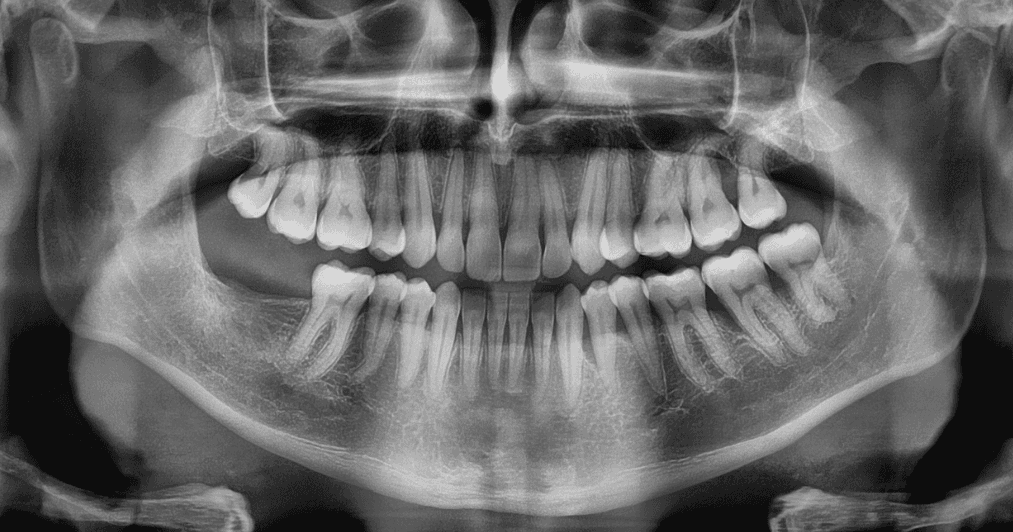

X-RAYS